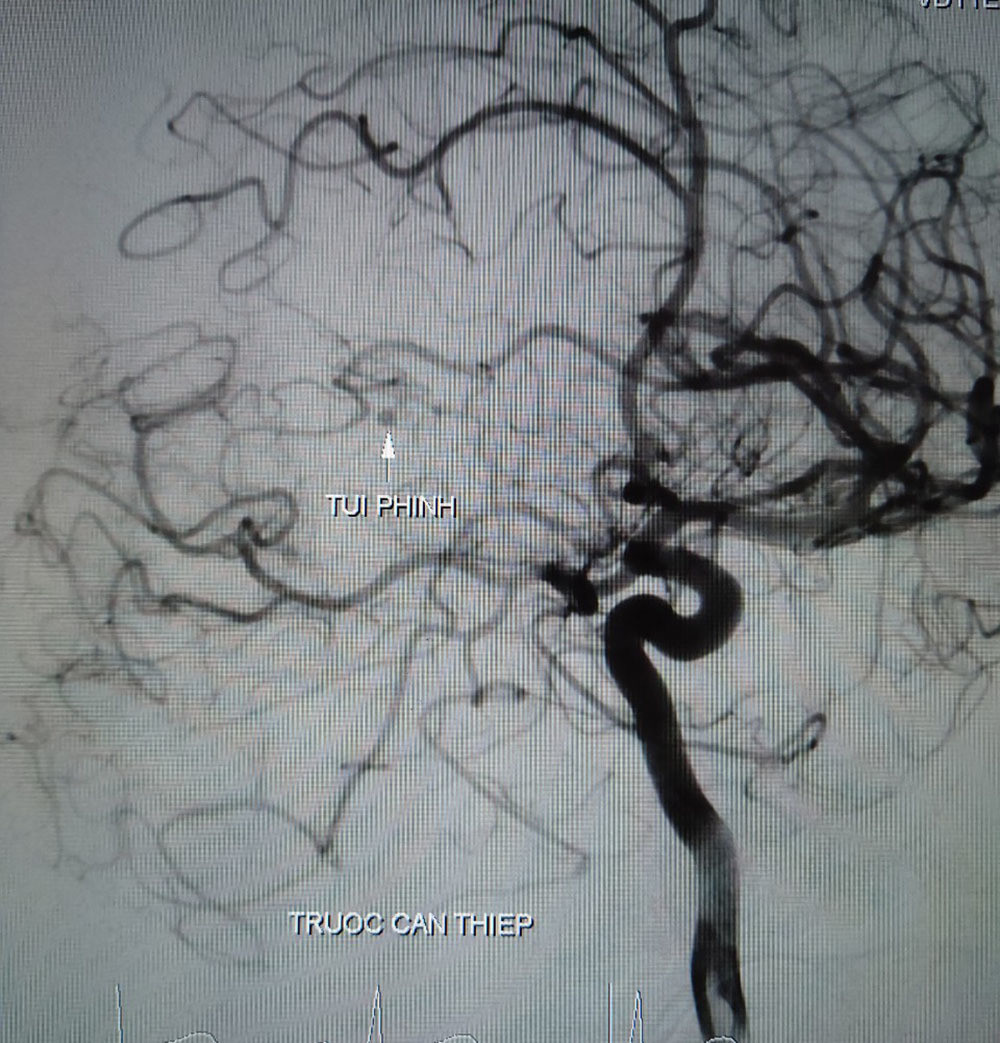

Hình ảnh túi phình mạch não của bệnh nhân T. trước khi can thiệp

Qua hội chẩn, bác sĩ quyết định thực hiện chụp mạch máu kỹ thuật số xóa nền. Kết quả cho thấy, có búi dị dạng động tĩnh mạch não vị trí gần não thất bên ở bên trái.

Bác sĩ đã tiến hành nút dị dạng và bảo toàn các nhánh mạch máu lành. Sau khi nút dị dạng thành công, bệnh nhân được tiếp tục phẫu thuật để dẫn lưu máu và dịch trong não ra ngoài làm giảm áp lực trong sọ.